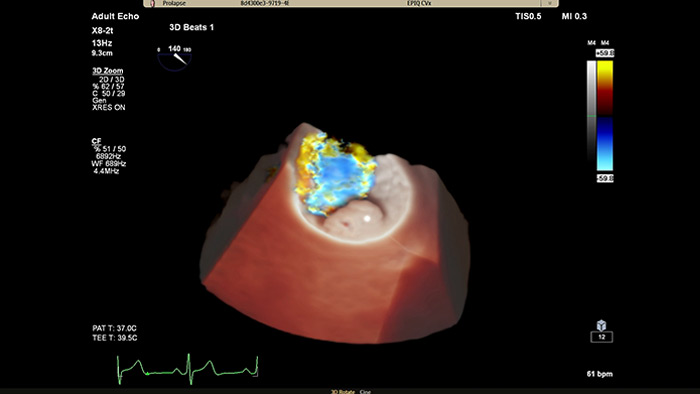

EPIQ CVx – TrueVue Color

Verbesserte Darstellung von Strukturen und Blutfluss mit TrueVue Color

• Besseres Verständnis von strukturellen Veränderungen des Herzens und der davon betroffenen Blutflüsse zur sicheren Durchführung des geeigneten Verfahrens

• Zweifelsfreie Beurteilung der Mitralklappe mit erweiterter Automatisierung zur Bereitstellung der verschiedenen Messwerte und funktionalen Daten, die für aussagekräftige Echoinformationen benötigt werden